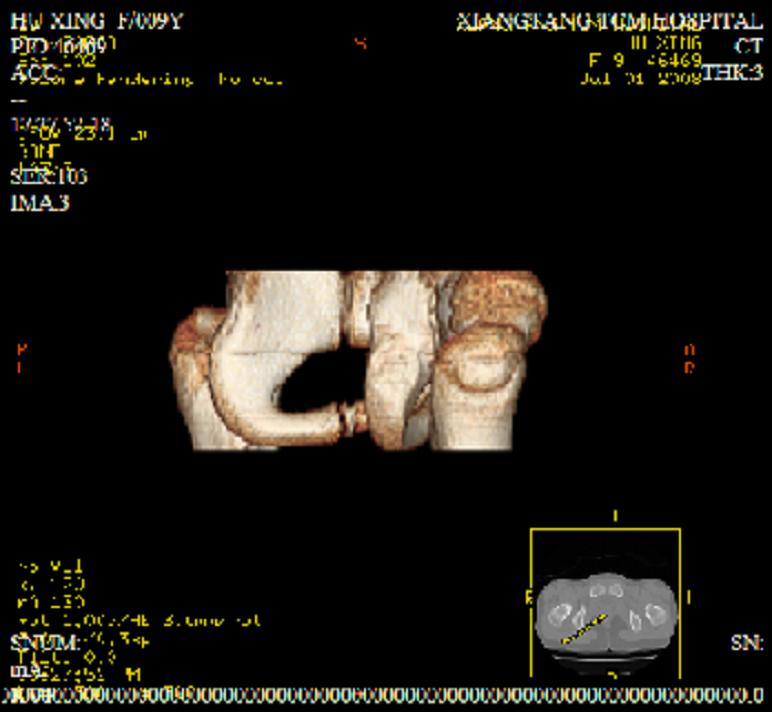

以下是引用zxd95在2008-7-2 10:06:00的发言:[br]左耻骨下支局部骨质破坏,内见小条状小骨片,周围肌间隙模糊,左闭孔内外肌肿胀。[br]儿童患者,首先考虑结核性,以骨质破坏为主(其内小条状小骨片解释为死骨)。[br]鉴别:[br]1、化脓性病变以增生为主;[br]2、肿瘤性病变:良性肿瘤不会有周围软组织的肿胀、模糊;恶性肿瘤病变骨皮质破坏、中断;[br]3、肿瘤样病变:一般也无周围软组织的改变。[br]建议查肺部及结核相关实验室检查。